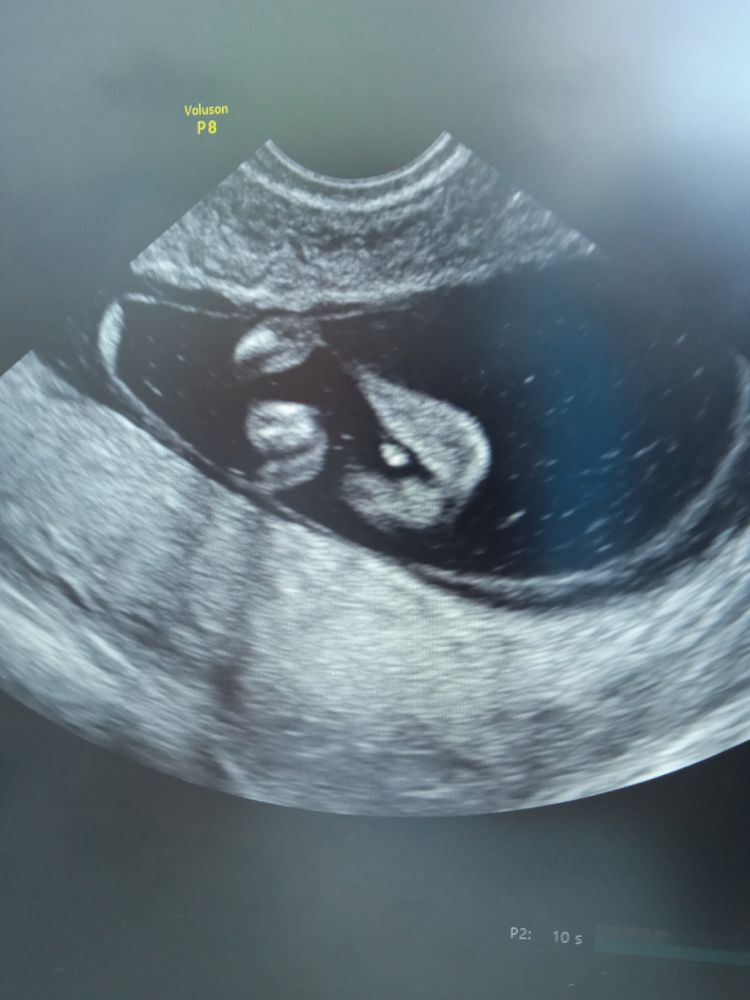

УЗИ на 13 неделе

Доброго времени суток была на УЗИ ,13недель ,сказали что похож на мальчика , сдала анализы девочка кому и чему верить ? У кого нибудь были ошибочные анализы пол плода